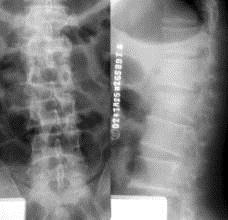

病历摘要: 患者×××,男性,21岁,不慎从3米高处坠落,双足着地,出现双足跟肿胀疼痛,腰痛不能站立。查体:腰1棘突有压痛和叩击痛,双足足跟部肿胀,触痛(...

问题 病历摘要: 患者×××,男性,21岁,不慎从3米高处坠落,双足着地,出现双足跟肿胀疼痛,腰痛不能站立。查体:腰1棘突有压痛和叩击痛,双足足跟部肿胀,触痛(+),双下肢感觉正常,双足伸足母、伸趾正常,双膝关节伸屈正常。 胸腰椎骨折常见的并发症有哪些?

选项 A、下肢静脉栓塞 B、尿路感染 C、肺部感染 D、马尾神经损伤 E、褥疮 F、脊髓损伤

答案 ABCDEF